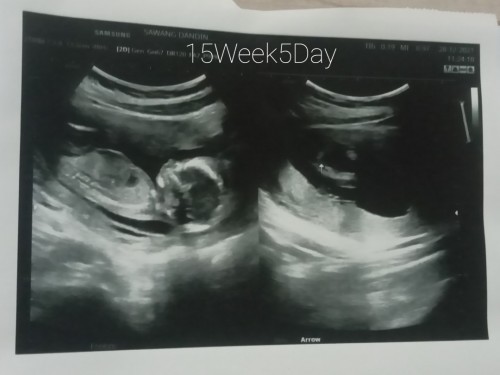

ซาวด์ตอน15+5wค่ะ ตอนนี้19w แล้ว ลูกสาวจ้า